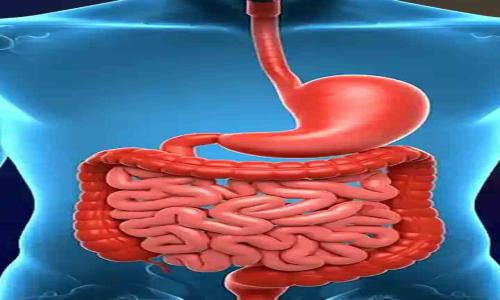

జీర్ణ వ్యవస్థను మెరుగుపర్చడంలో అల్లం ఎంతగానో ఉపయోగపడుతుంది. గ్యాస్, అజీర్తి, బ్లోటింగ్, మలబద్ధక సమస్యలకు చెక్ పెడుతుంది.